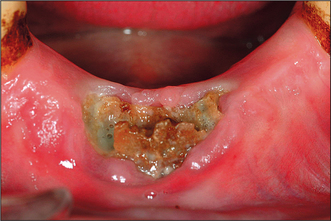

Dry socket

Dry socket (alveolar osteitis, alveolitis sicca dolorosa, infected socket) occurs after about 3% of routine extractions. It is recognized by pain at the site of extraction, often aching or throbbing in nature but remarkably constant in severity (including during the night), starting within a day or so of a tooth extraction. The pain is often resistant to common analgesics. Examination reveals a socket partly or totally devoid of blood clot with exposed, rough, painful bone (Fig. 4.31). Greyish remnants of clot may be present. The surrounding mucosa and the whole alveolus may be red, swollen and tender. Inflammation spreads through the alveolus mesiodistally, resulting in tenderness of the adjacent teeth to pressure. Occasionally a patient will believe that the wrong tooth has been extracted because of the pain in the adjacent tooth. Be aware that misdiagnosis can occur. The mouth smells and tastes foul (a smell of anaerobic bacterial activity or rotting meat). There may be a local lymphadenitis, but severe systemic response in the form of fever is rare.

image

Fig. 4.31 Dry socket.

If no treatment were provided the condition would eventually resolve spontaneously, but it may take up to 4 weeks and during that time the pain would persist. Similar pain is experienced whenever an area of bone is left exposed in the mouth and usually settles when the exposed (and non-vital) bone is either eventually covered by granulation tissue or is separated from the underlying bone and sequestrated. A few untreated cases of dry socket may progress to infection that spreads through the bone marrow (osteomyelitis).

There is obviously a bacterial component to this condition. Its incidence may be reduced by the prophylactic administration of metronidazole, or by the irrigation of the gingival crevice with chlorhexidine before extraction. It should be noted, however, that routine prophylactic administration of antibiotics before extraction is not justified. There are similarities to acute ulcerative gingivitis in the high spring and autumn prevalence, frequency in smokers and possible relationship to female sex hormones. However, some aspects of the condition’s behaviour are not so obviously infective in nature.

The condition is most prevalent in patients in their fourth decade. It is more common after extractions of posterior and difficult teeth and seen more often in the lower jaw than the upper. Dry socket is more likely to occur after extractions under local anaesthesia than under general anaesthesia and is less frequent after multiple extractions.

It is probable that the condition represents the outcome of a mixture of disease processes in which trauma, local fibrinolysis and bacterial clot degradation all play a part. Some patients are particularly prone to dry socket, without any other evident medical problem.

Investigation need not be extensive; the condition can usually be diagnosed confidently on clinical grounds. A radiograph is valuable, both as a baseline against which to check bone change, should there not be a rapid resolution, and to assure the dentist and patient that no root has been left behind.

Treatment of the condition is primarily symptomatic. The socket should be irrigated with warm saline to remove the debris. A variety of antiseptic dressings is available to cover the exposed bone. A proprietary, eugenol-containing, soft, fibrous paste can be tucked into the coronal part of the socket to cover the bone. It can be left in situ and is usually shed spontaneously from the socket over a few days. Pain relief is usually very effective within hours. If relief is not achieved in a reasonable time, repeat irrigation and dressing of the wound is usually effective. Alternative dressings (each of which must be removed about a week later) include Whitehead’s varnish on ribbon gauze, Bismuth Iodoform and Paraffin Paste on gauze (which may have lidocaine (lignocaine) paste added to it). Zinc oxide and eugenol cements are not recommended as they tend to adhere strongly to the bone.